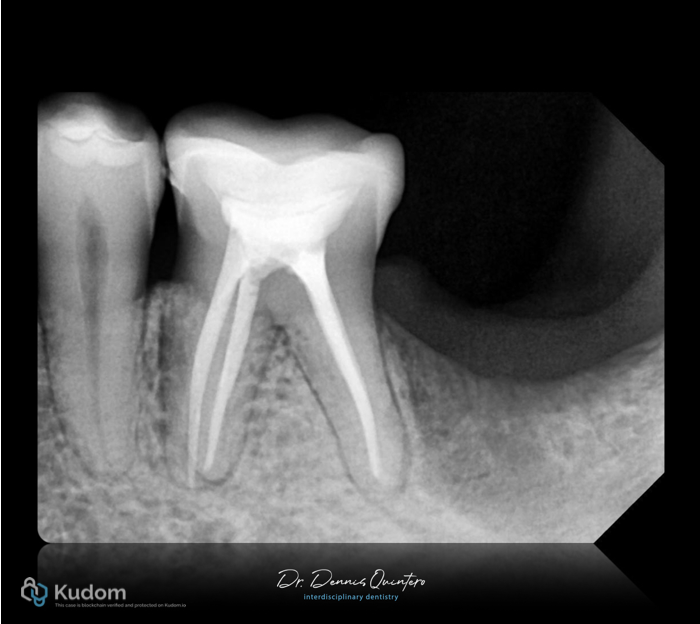

Fig. 1

. Tooth 3.6

. Initial X-ray with deep provisional material close to the pulp.